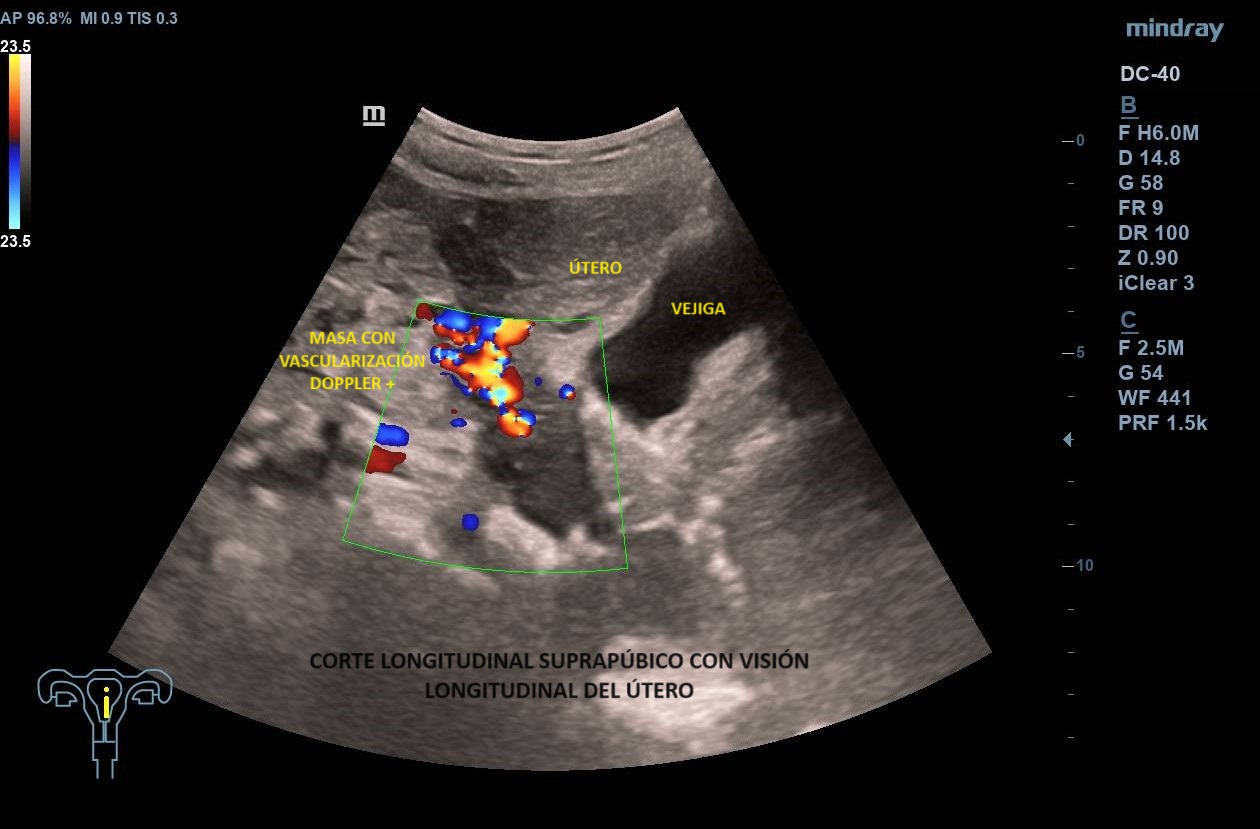

Ecografía abdominal clínica: Masa heterogénea que ocupa todo el abdomen, de aspecto sólido, vascularizada con zonas hipoecoicas-anecoicas en su interior. Riñones con eco-estructura sin alteraciones, hígado sin LOES. Vejiga sin engrosamiento de paredes, útero parcialmente visible. Anejos y retroperitoneo no valorables. No líquido libre.

Se deriva a urgencias donde realizan ecografía transvaginal confirmando presencia de masa que parece depender de anejo derecho. Solicitan TAC toraco-abdomino-pélvico objetivando «masa abdominal gigante de dudosa dependencia ovárica, no pudiendo descartar liposarcoma abdominal». Citan a la paciente para RM donde se demuestra contacto pero no dependencia de masa abdominal, probable liposarcoma, de anejo derecho, de características normales. Analítica con marcadores tumorales sin alteraciones.

Los leiomiomas uterinos son el tumor más frecuente de pelvis en la mujer. La ecografía es la primera línea de estudio. Habitualmente s

e describen como masas bien delimitadas redondeadas hipoecoicas con sombra acústica, aunque también pueden tener áreas isoecoicas e hiperecoicas. Pueden presentar necrosis central (áreas anecoicas) o calcificaciones, sin implicar malignización. El Doppler-color suele mostrar una distribución irregular de los vasos. El diagnóstico definitivo es el anatomo-patológico.